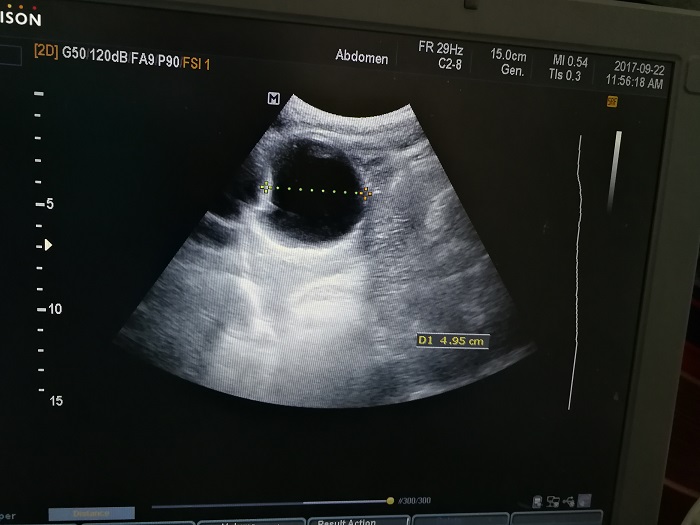

扎西(化名),男,15歲,包蟲病篩查陽(yáng)性,牧區(qū)孩子,家里有牦牛20頭、羊200只,狗1條,牛羊自家屠宰,飲用河水。

●革吉縣初級(jí)中學(xué)篩查點(diǎn) · B超現(xiàn)場(chǎng)圖片

除了包蟲病篩查外,連續(xù)三天的學(xué)校體檢我醫(yī)療隊(duì)發(fā)現(xiàn)腎積水、腎囊腫、腎結(jié)石的學(xué)生患者較多,我們將體檢到的相關(guān)臟器疾病同時(shí)間反饋給了班主任,讓他們密切觀察病情,及時(shí)通知家長(zhǎng)。劉冬梅醫(yī)生建議,學(xué)校要組織學(xué)生多飲水,同時(shí)多加觀察本地水質(zhì)情況。

本次篩查,革吉縣初級(jí)中學(xué)共篩查學(xué)生498例,陽(yáng)性3例,疑似2例。